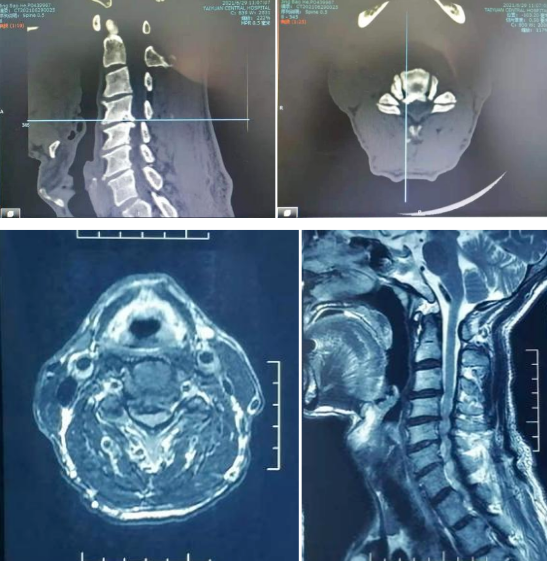

術前,影像學資料顯示王大爺的頸4/5椎間盤突出,骨贅形成,頸4至6椎管狹窄,脊髓受壓,髓內有高信號。

術后,影像顯示C4/5椎體后緣骨贅,頸4-6椎管以擴大,脊髓周圍有腦脊液填充。